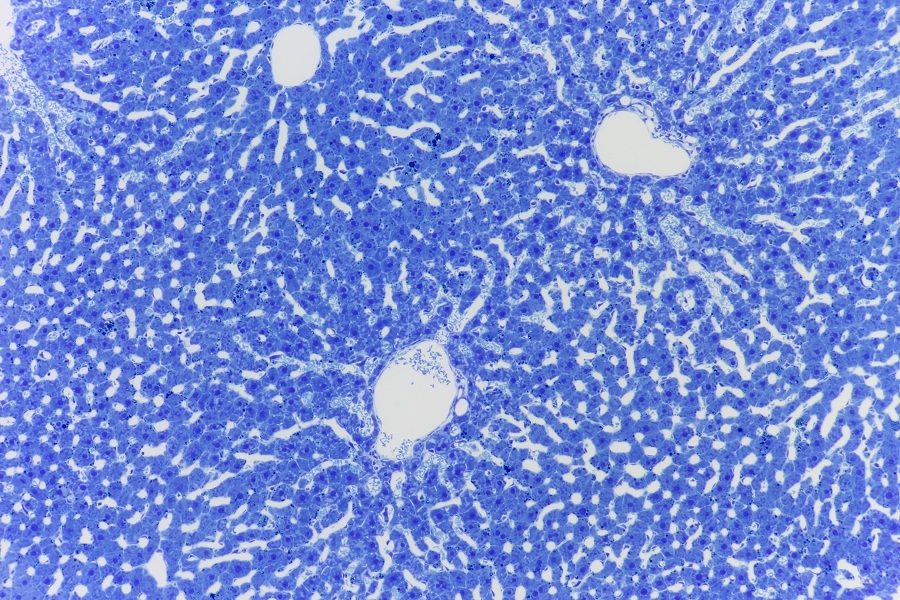

Bild3,

Übersicht Bild. Objektiv Leitz plan Fluotar 4x.

Bild4,

Übersicht Bild. Objektiv Leitz plan Fluotar 10x.